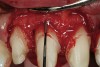

Figure 8  After initial closed-flap bony correction, a full-thickness mucoperiosteal flap was raised to visualize the accuracy of the osseous correction and observe the tooth surface and condition of the bony crest as a result of the procedure. It can be seen that the surface of the root is unscathed. The osseous crest was accurately repositioned 3 mm apically from the restorative margin, following its exact contour.

Figure 8